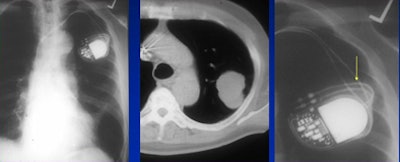

|  |

| False-positive: Loculated pericardial fluid is often misread as a lung mass. |